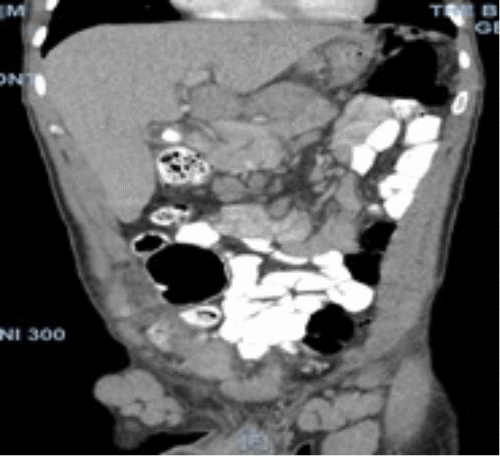

On physical examination, his vitals were within normal limits. He was very thin and had diffuse palpable lymphadenopathy in the cervical and inguinal regions and a large mobile left cheek mass. His abdominal exam was benign, with no anterior abdominal pain but rather bilateral flank pain. The patient's leukocytosis was 13,000 k/cm2, with the remainder of his labs within normal limits; the cluster of differentiation 4 (CD4) count was 2670, and the viral load was 1,391,823. HTLV-I/HTLV-II antibodies were positive. A CT of the abdomen and pelvis with oral and intravenous (IV) contrast was obtained, showing acute tip appendicitis (Figure 1) and extensive bulky gastrohepatic, periportal, peripancreatic, retroperitoneal/para-aortic, bilateral iliac chain, and bilateral inguinal lymphadenopathy (LAD) (Figure 2) with mild splenomegaly suggestive of lymphoma. A CT maxillofacial scan to evaluate his cheek mass also demonstrated extensive bulky cervical lymphadenopathy as well as an enlarged mandibular mass (Figure 3). Of note, the patient had a CT scan performed one year prior that showed an appendix with the same diameter but no local inflammation (Figure 4).

Figure 1. CT Scan: Tip Appendicitis in Pelvis. Published with Permission